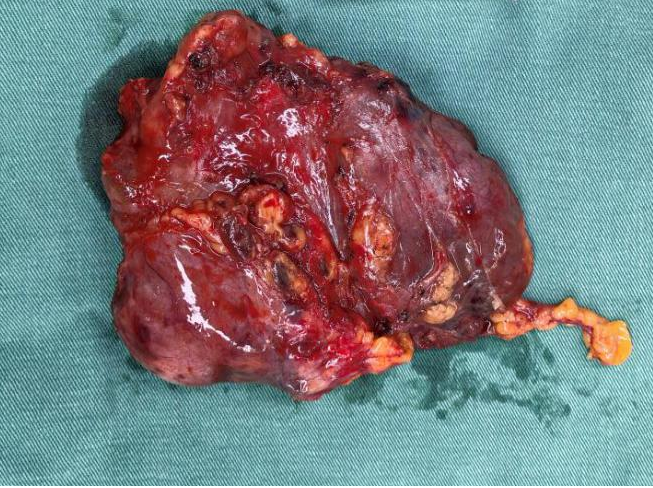

被切除的腫瘤

術(shù)前胸心血管外科團(tuán)隊(duì)聯(lián)合多學(xué)科評估風(fēng)險(xiǎn),確定手術(shù)方式、風(fēng)險(xiǎn)防范與圍手術(shù)期應(yīng)急方案。術(shù)中,胸心血管外科副主任呂忠柱主任醫(yī)師主刀,通過正中胸骨切開手術(shù),憑借精準(zhǔn)操作避開致命陷阱,成功拆除前縱隔巨大腫瘤、完成胸腺擴(kuò)大切除,同時(shí)清掃了周圍淋巴結(jié),在保證安全的前提下達(dá)到了R0切除。手術(shù)過程順利,術(shù)后患者順利脫機(jī)拔管,已順利康復(fù)出院。